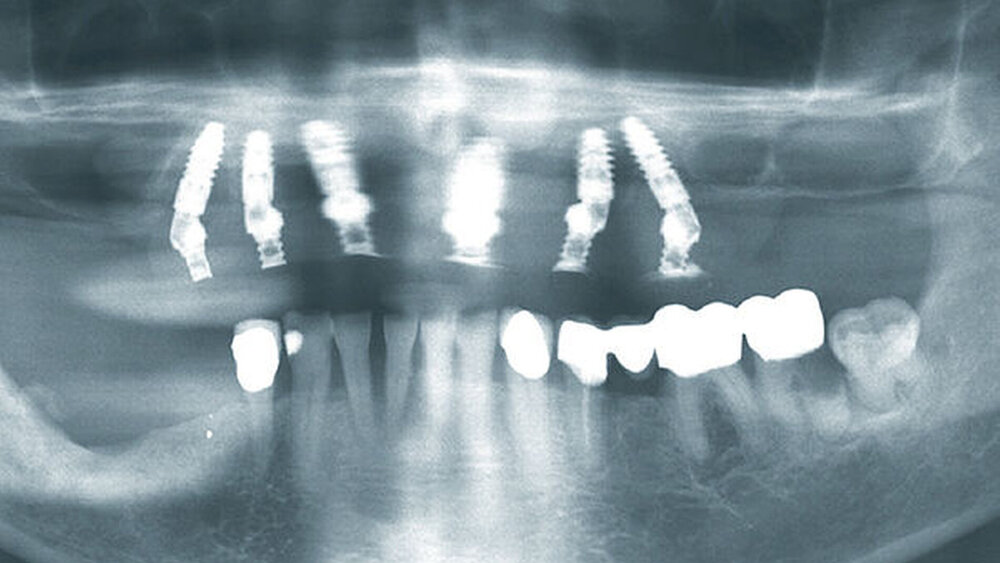

Buhtz: Korrekt, die Voraussetzung ist lediglich die Generierung von DICOM- und STL-Daten, die im Computer exakt übereinandergelegt werden können. Dann erfolgen die Behandlungsplanung wie gewohnt mit ICX-Magellan und die provisorische ‧Versorgung mit dem präfabizierten, chairside hergestellten verklebten PMMA-Provisorium (ICX-‧Smile‧bridge). Seit eineinhalb Jahren arbeiten wir zudem mit dem medentis Fräszentrum Denta5 zusammen.

Buhtz: Egal, wie viele Implantate ich wo setze – am Anfang stehen in meiner Praxis meist eine DVT-Aufnahme und eine 3D-Planung. Ohne Schablone setze ich heute nur noch in absoluten Ausnahmefällen ein Implantat. Die Sicherheit und die gute Planbarkeit reduzieren die Angst der Patienten vor dem Eingriff und erleichtern die Aufklärung. Artefaktarme DVT-Aufnahmen sind natürlich für die Präzision entscheidend.

Die ideal prothetisch ausgerichtete Implantatposition ist der wohl wichtigste Erfolgsfaktor in der Implantologie. Mit ICX-Magellan lässt sich das einfach, schnell und kostengünstig realisieren.